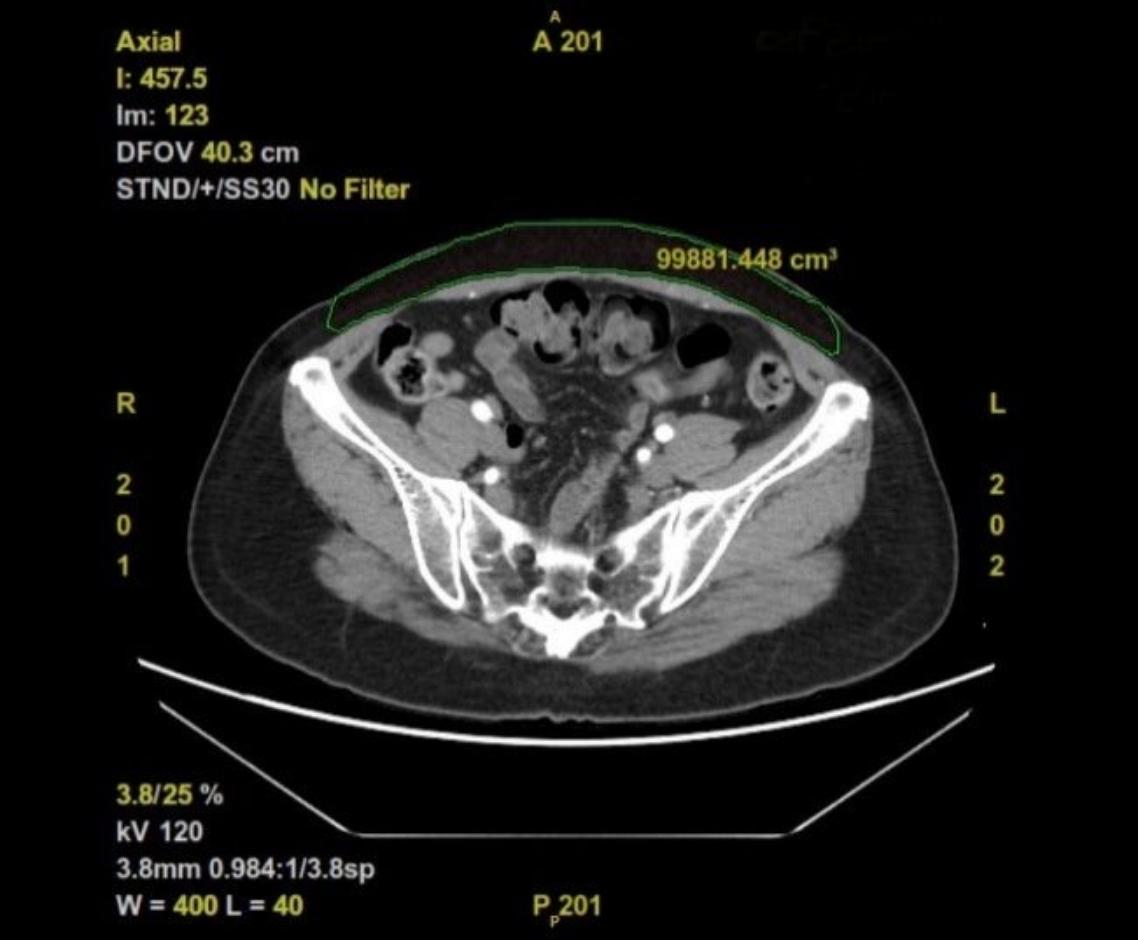

乳房重建的2大方向,為義乳和自體組織重建,端視病人的需求和考量。周宣宇醫師說,目前自體組織重建的主流,是採用深下腹動脈穿通枝皮瓣來進行,跟傳統的腹直肌皮瓣重建相較,對於肌肉的破壞較小,也較不會有疝氣發生。但因為深下腹動脈穿通枝皮瓣是游離皮瓣,需要重新吻合血管,因此手術技術門檻較高,時間較長,且術後一開始的恢復期也較久。

不過由於使用的是自體組織,病人恢復後較為自然,也無義乳相關感染、排斥、移位、破裂或淋巴癌風險,並可接受輔助放射線治療。惟有後續若有生育計劃的女性需審慎與醫師討論,以避免懷孕期間腹部擴張的過程產生腹壁疝氣,進而影響胎兒及媽媽的安全。